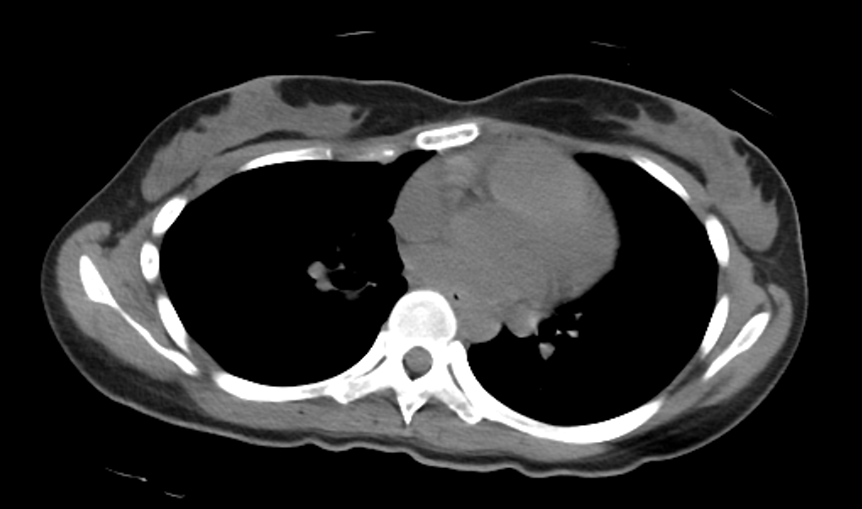

巨乳には乳腺型と脂肪型があるってポストが流れてきたけどそれぞれの参考画像がないとなんとも…… 参考画像がないとなんとも……!

You have both, but some just have more glandular (parts that make milk) than fat. If I squeeze and feel dense parts, that’s the glandulartissue, but if I squeeze and it is soft/plush, that is fat.